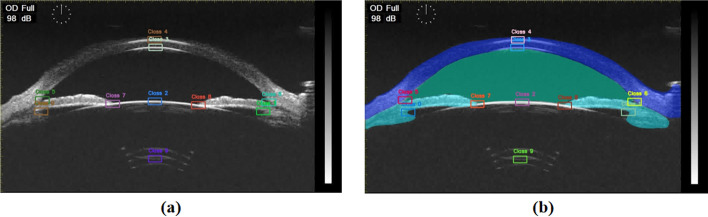

Background: Accurate measurement of anterior segment parameters is crucial for diagnosing and managing ophthalmic conditions, such as glaucoma, cataracts, and refractive errors. However, traditional clinical measurement methods are often time-consuming, labor-intensive, and susceptible to inaccuracies. With the growing potential of artificial intelligence in ophthalmic diagnostics, this study aims to develop and evaluate a deep learning model capable of automatically extracting key points and precisely measuring multiple clinically significant anterior segment parameters from ultrasound biomicroscopy (UBM) images. These parameters include central corneal thickness (CCT), anterior chamber depth (ACD), pupil diameter (PD), angle-to-angle distance (ATA), sulcus-to-sulcus distance (STS), lens thickness (LT), and crystalline lens rise (CLR).

Methods: A data set of 716 UBM anterior segment images was collected from Tianjin Medical University Eye Hospital. YOLOv8 was utilized to segment four key anatomical structures: cornea-sclera, anterior chamber, pupil, and iris-ciliary body-thereby enhancing the accuracy of keypoint localization. Only images with intact posterior capsule lentis were selected to create an effective data set for parameter measurement. Ten keypoints were localized across the data set, allowing the calculation of seven essential parameters. Control experiments were conducted to evaluate the impact of segmentation on measurement accuracy, with model predictions compared against clinical gold standards.